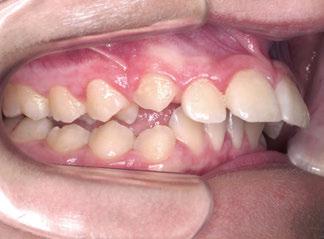

La respiración bucal es muy frecuente en niños con asma y surge como una función adaptativa, ya que tienen dificultad respiratoria. Puede implicar cambios de postura a nivel cervical, afectando al crecimiento del niño; además de alteraciones en el crecimiento de maxilares y en los m ú sculos orofaciales, la posición baja de la lengua detiene el crecimiento transversal, originando paladar ojival y mordida cruzada posterior. A nivel anterior, la alteración en la posición lingual provoca deglución atípica.

Castañeda-Zetina y cols. realizaron un estudio para comparar las maloclusiones en niños asmáticos y sanos, en el cual se incluyeron 186 pacientes de entre 5 y 12 años. Los resultados obtenidos fueron que más del 50% de los niños asmáticos tienen respiración oral. Las principales alteraciones oclusales presentadas eran mordida abierta anterior y mordida cruzada posterior, menos frecuente; además de una menor frecuencia de clase III, solo un 11,6%, ya que el cambio postural de estos pacientes favorece la entrada del aire inclinando la cabeza hacia atrás y favoreciendo la aparición de clase II al posterorrotar la mandíbula. Estas modificaciones posturales van a producir alteraciones maxilares y desequilibrio en los m ú sculos periorales; por ello, su detección precoz ayudará a resolver el problema con un abordaje multidisciplinario y dando armonía al complejo dentoesquelético (56).